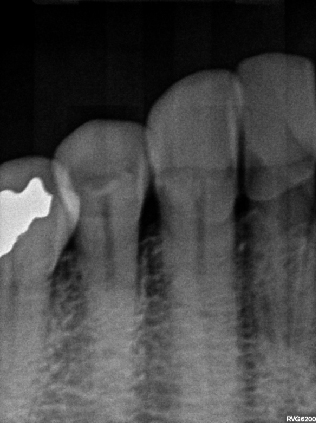

Post-Treatment X-ray